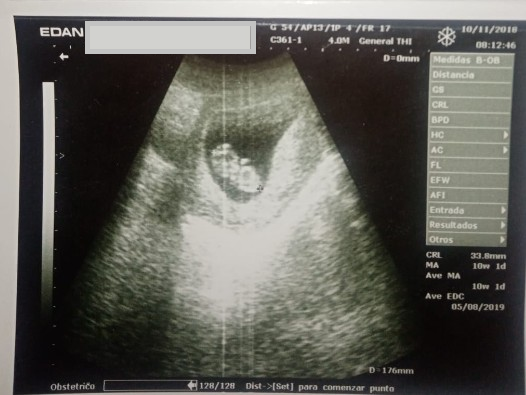

Progenitora acudió a siete controles prenatales, realizándose cinco ecografías, la primera a las 6 semanas de gestación, la segunda, a las 10 semanas (Figura 1), las cuales fueron normales. Las siguientes ecografías reportaron dificultad para observar extremidades fetales.

Ecografía a las 6 semanas de gestación, sin patologías aparentes.